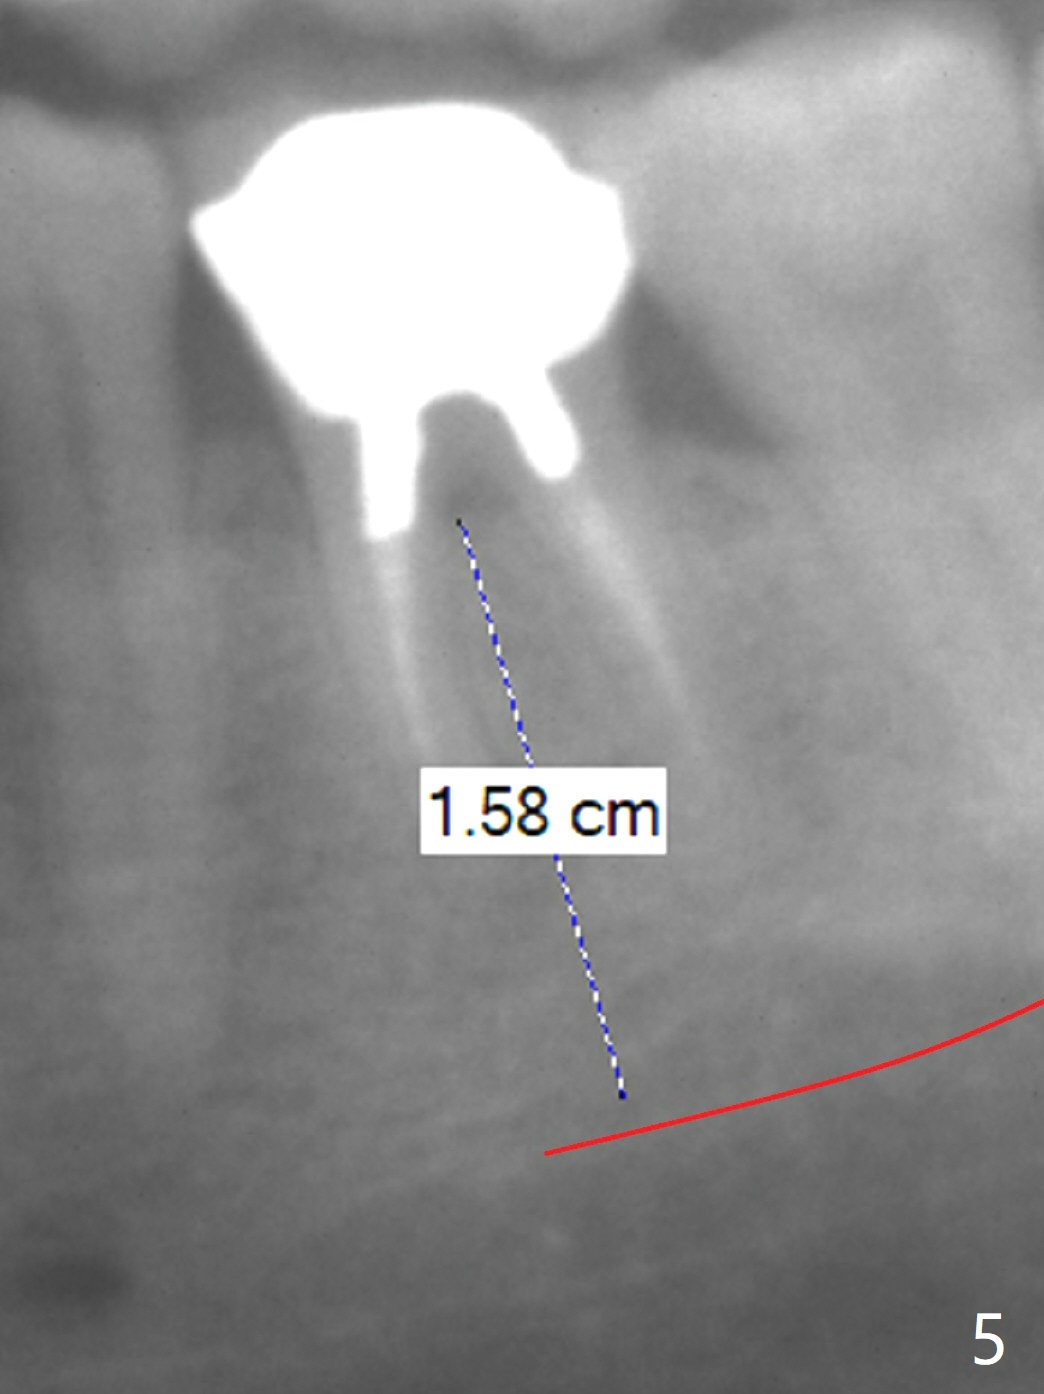

A 53-year-old man has had pain with chewing gums at #19 for 3 years (Fig.1). While a 7x17 mm implant was immediately placed at #30 six years earlier, a 5x17 mm one will be inserted at #19 as lingual as possible to reduce buccal thread exposure (Fig.2). The whole tooth will be extracted before osteotomy in the septum, since the roots in the sockets do not help free hand osteotomy unless the crown breaks off during extraction. Initial depth will be 14 mm. Use Tatum 17 mm drills. Drills are more likely deviated to the mesial socket with large PARL (Fig.1 *). Use visual acuity to correct deviation as early as possible. Pack sticky bone into the mesial bony defect for repair. Take photos of #19 and 30 for buccal recession and fistula if present. It is safe to place a 11 mm long bone level implant (Fig.3,5). It would be ideal to establish initial osteotomy as indicated by the red arrow (Fig.4).